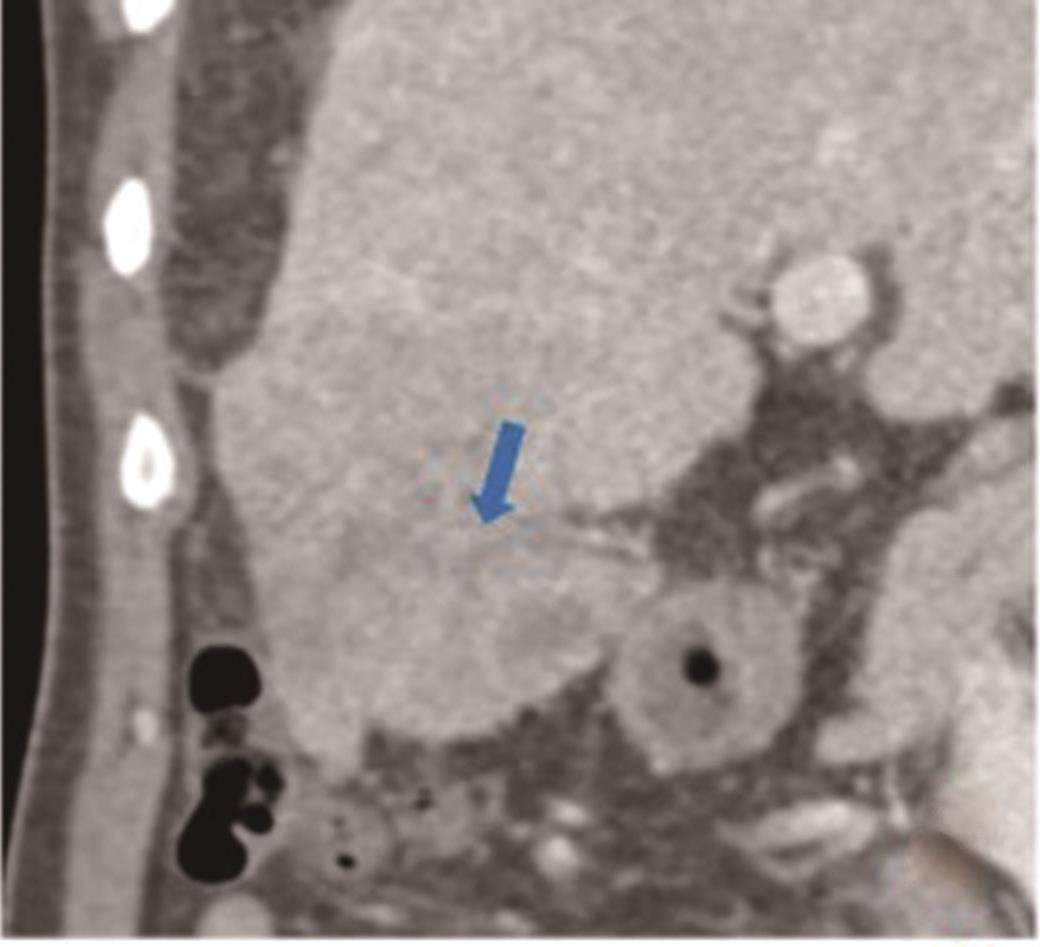

• 探讨增强CT在鉴别胆囊癌侵犯肝脏与肝癌累及胆囊病变中的应用价值

摘要:目的 探讨增强电子计算机断层扫描(computer tomography,CT)在胆囊癌侵犯肝脏与肝癌累及胆囊病变中的鉴别诊断价值。方法 收集2012年2月到2022年2月重庆医科大学附属第一医院115例患者临床及影像学资料,其中胆囊癌侵犯肝脏病例69例,肝癌累及胆囊病例46例,记录性别、年龄、肿瘤大小、肿瘤边界、胆囊形态、肝硬化、胆管扩张、肿瘤内或胆管系统内高密度影、门静脉癌栓、强化方式、强化程度、淋巴结肿大及远处转移共13个观察指标,并进行统计学分析。结果 性别(P=0.007)、年龄(P=0.002)、肿瘤大小(P=0.003)、肝硬化(P<0.001)、肿瘤内或胆管系统内高密度影(P=0.013)、门静脉癌栓(P<0.001)、强化方式(P<0.001)及淋巴结肿大(P=0.034)有统计学差异。通过回归分析筛选出年龄(敏感度为0.812,特异度为0.457)、肿瘤大小(敏感度为0.630,特异度为0.696)、门静脉癌栓(敏感度为0.326,特异度为0.957)、淋巴结肿大(敏感度为0.681,特异度为0.522)为显著分类指标,联合4个观察指标的参数绘制受试者工作特征(receiver operating characteristic,ROC)曲线,曲线下面积(area under the curve,AUC)为0.770,敏感度为0.674,特异度为0.826。结论 增强CT在鉴别胆囊癌侵犯肝脏与肝癌累及胆囊病变时,性别、年龄、肿瘤大小、肝硬化、肿瘤内或胆管系统内高密度影、门静脉癌栓、强化方式及淋巴结肿大有鉴别价值,同时结合年龄、肿瘤大小、门静脉癌栓及淋巴结肿大有助于提高鉴别诊断能力。